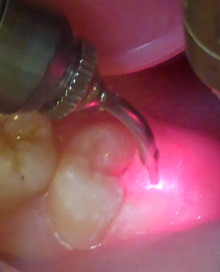

そこで、レーザーを用いた

虫歯治療を紹介します。

エルビームヤグレーザー

と呼ばれる最新レーザーです。

虫歯の部分のみを蒸散できます。

麻酔なしでできます。

音は 「パチパチ」

痛みはまったくありません。

欠点は 削りとるより 若干時間がかかります。

レーザーで黒い虫歯をとりました。